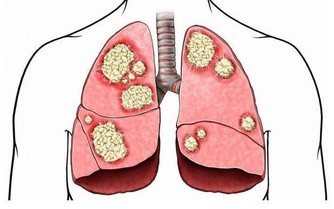

流感(Influenza)是一種由流感病毒引起的急性呼吸道感染,會導致發燒、喉嚨痛、肌肉痠痛、咳嗽、疲勞和食慾不振等症狀。當感染流感時,身體需要額外的營養來支持免疫系統對抗病毒,並加速復原。適當的飲食能夠幫助減輕症狀、提升能量,並促進康復。那麼,流感期間該吃什麼食物?有哪些營養素能幫助身體更快恢復?本篇文章將提供完整的流感飲食指南,幫助您早日恢復健康。